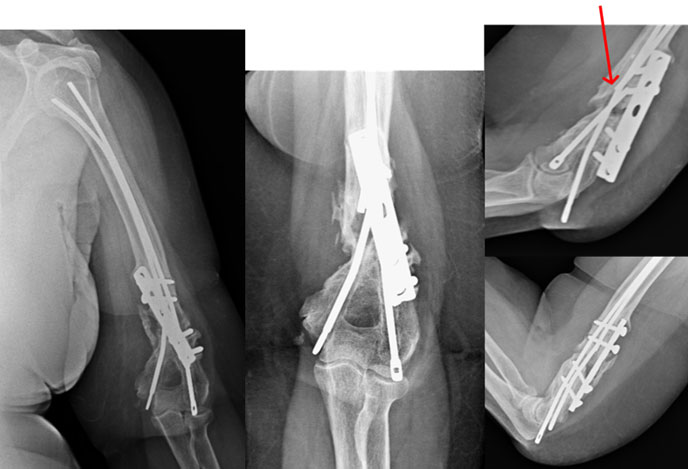

At presentation

This 58 year old lady had a fracture of the distal humerus (close to elbow) about 6 years back. She had already been operated twice for the fracture, once with the plate and second time the intra-medullary Ender’s nails were introduced supplementing the plate with bone grafting. She had pain at the fracture site and restriction of elbow movements.

The x-rays showed the fracture was not united. The screws were coming out and the Ender’s nails were broken (red arrow).